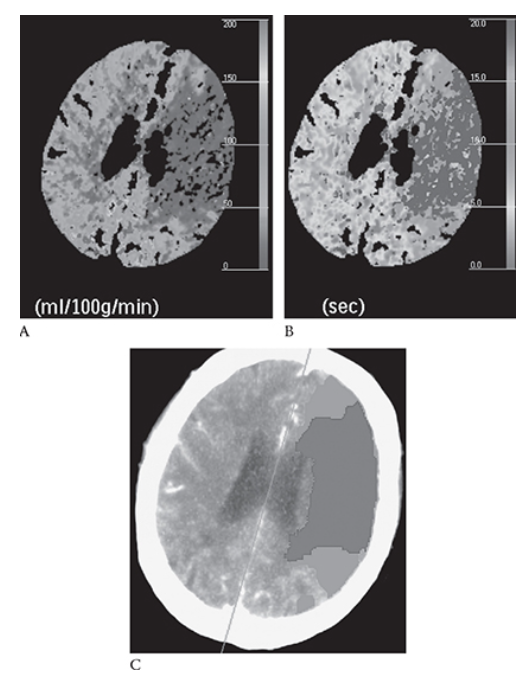

What is A

Ischemic Stroke. Same patient as in Figure 5 with the left MCA stroke. Shows decreased cerebral perfusion to this area (blue) Mean transit time is prolonged (blue)

What is B

Ischemic Stroke. Same patient as in Figure 5 with the left MCA stroke. Shows decreased cerebral perfusion to this area (blue) In image

What is C

Ischemic Stroke. Same patient as in Figure 5 with the left MCA stroke. Shows decreased cerebral perfusion to this area (blue) red represents an infarct; green represents the penumbra of threatened (at risk) ischemic brain that may potentially be saved with an intervention. (see Color Insert).